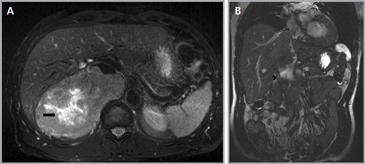

Figura 3. Glándula suprarrenal normal en resonancia magnética. (a) Cortes axial ponderado en T1 la señal de la glándula normal (flecha negra) es hipointensa respecto a la grasa retroperitoneal e isointensa respecto al parénquima hepático. (b) Cortes axial ponderado en T2 en que se muestra la glándula suprarrenal derecha (flecha blanca) y (c) corte coronal ponderado en T2 en que se muestra la glándula suprarrenal derecha (flecha blanca) y la glándula suprarrenal izquierda (flecha negra) con similares características de intendidad de señal. 3. Causas y prevalencia de las lesiones suprarrenales